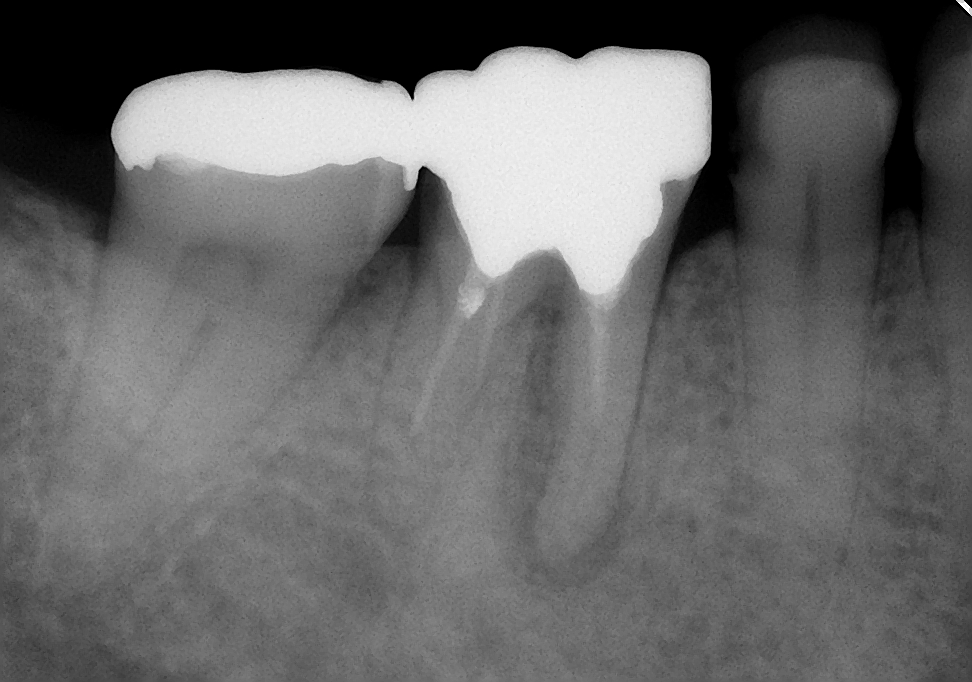

↑根の治療終了後

その後は、歯の土台を作りしっかり補強した後、仮歯を入れて咬んでも痛くないか、歯肉の腫れは再発しないかなど経過観察をしました。